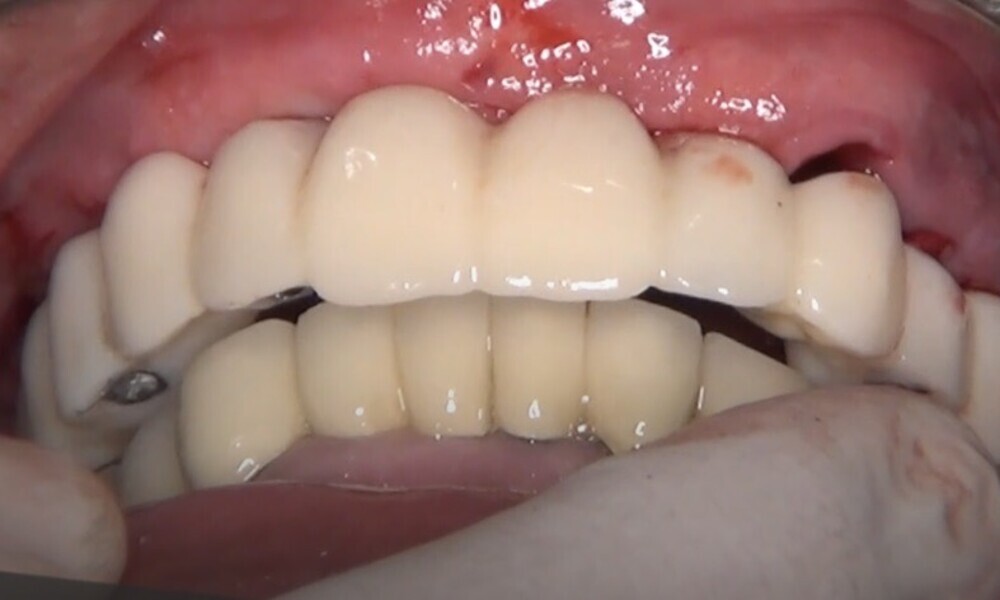

Employing a fully guided surgical protocol alongside a completely digital prosthetic workflow allowed for the precise design and milling of a PMMA provisional prosthesis (Figs. 34 & 35). The implant loading protocol implemented was immediate loading with equal distribution of forces across the entire prosthesis. The patient received the screw-retained provisional prosthesis on the same day. Temporary abutments (titanium copings) were placed on top of the screw-retained abutments. The spaces between the titanium copings and the provisional prosthesis were filled (Figs. 36–38). Any excess material was cut away, and the provisional prosthesis was subsequently polished to ensure a smooth finish (Fig. 39). The provisional prosthesis was then attached and securely fixed to the titanium copings to a 15 N cm torque (Fig. 40). Oral hygiene instructions were provided, and the occlusion was assessed (Figs. 41 & 42). A final control radiograph was obtained and confirmed that all parameters were within normal limits (Fig. 43).

During follow-up visits, the patient exhibited excellent healing and no postoperative complications (Fig. 44). The provisional prosthesis demonstrated optimal fit and stability, enhancing function and the patient’s comfort.

Four months later, we proceeded with the final prosthetic procedure based on clinical and radiographic evidence confirming osseointegration. The case was completed using Straumann RevEX scan bodies for a full monolithic design with a completely digital workflow. First, an intra-oral scan of the opposite arch was taken, followed by an intra-oral scan with the screwed-in temporary abutments. An intra-oral bite scan and an intra-oral scan of the soft tissue with the screw-retained abutments in place were then taken. The reverse scan bodies were attached to the provisional prosthesis, which was scanned extra-orally. Next, the prototype and verification jig were designed, followed by the milling of the prototype and verification jig (Figs. 45 & 46).

During the next visit, the milled prototype and verification jig were tried in, and the design and manufacturing of the final prosthesis were completed (Figs. 47 & 48). The final abutment utilised was Variobase for bridge (Straumann), placed on top of the screw-retained abutments. The material chosen for the final prosthesis was monolithic zirconia (Figs. 49 & 50).